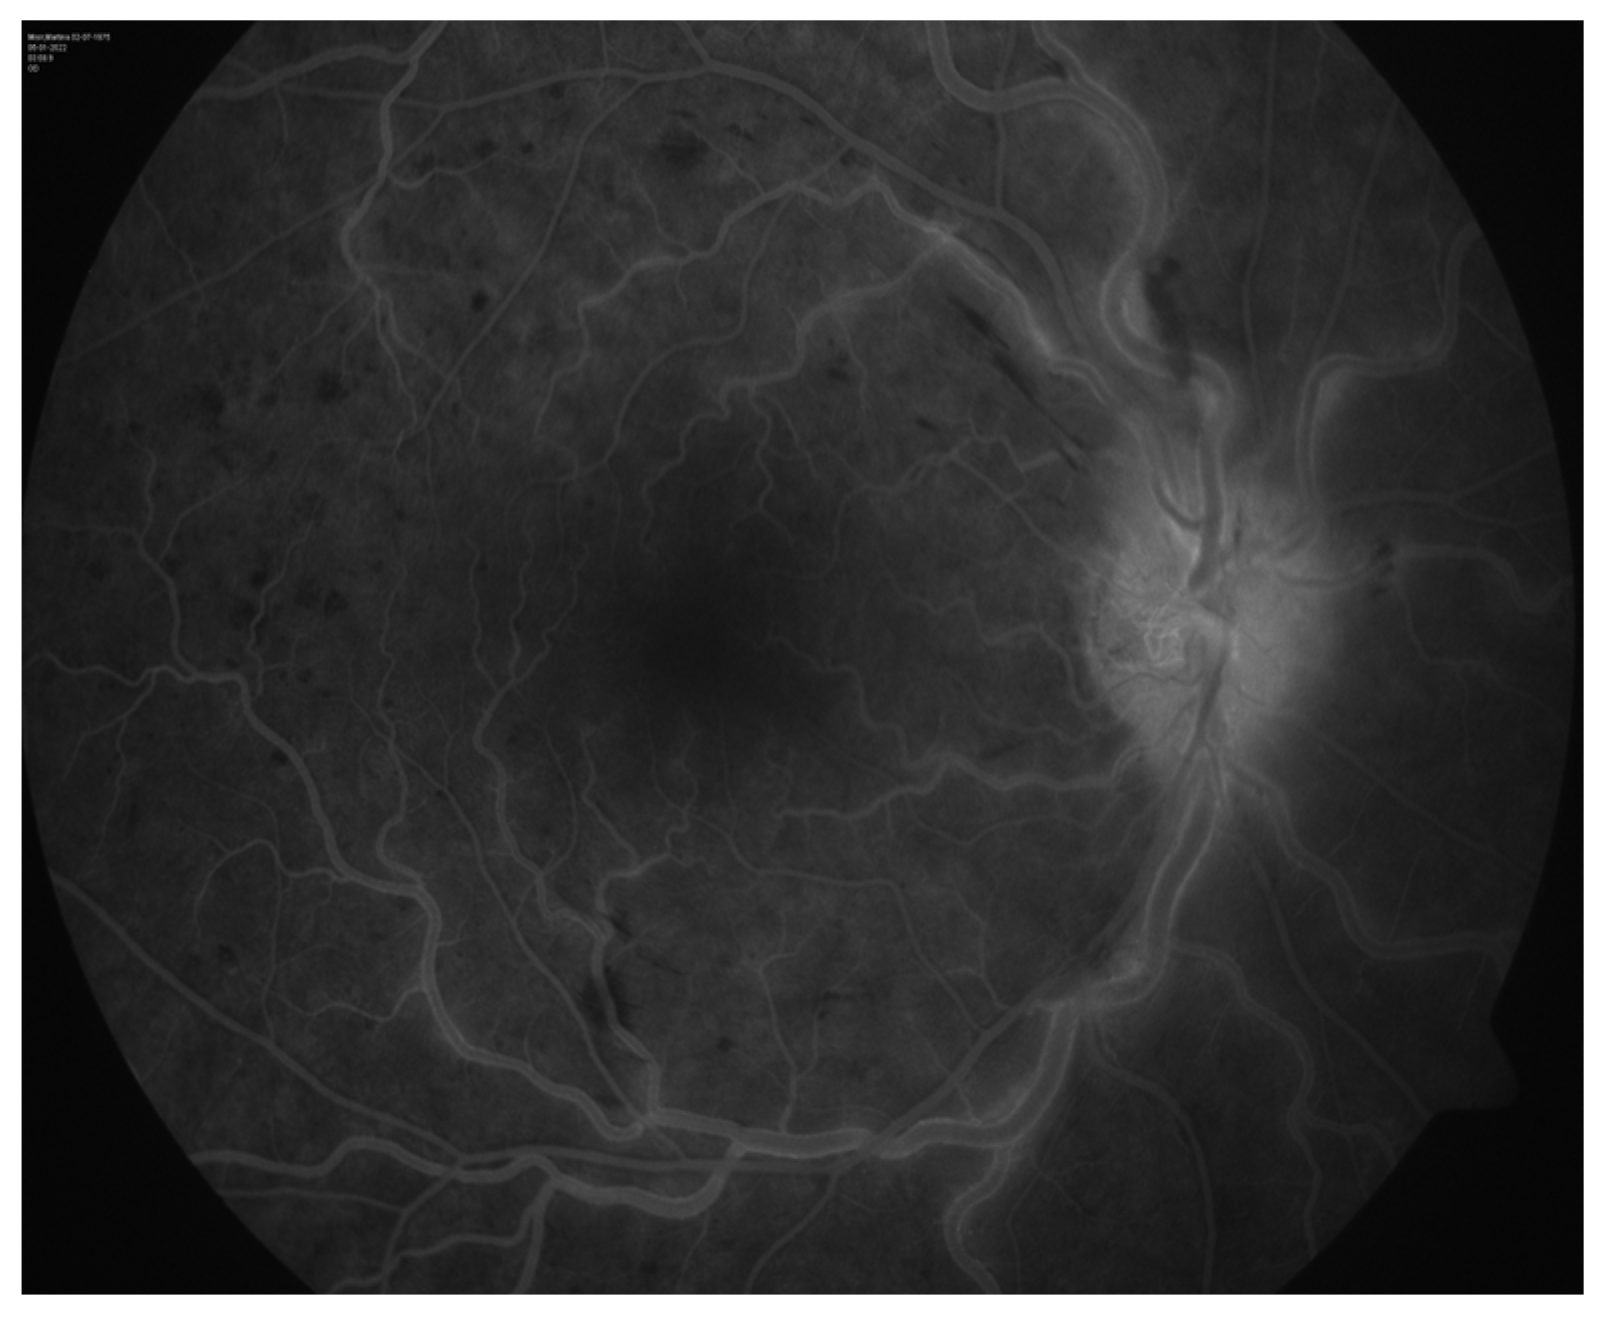

Concurrent Onset of Central Retinal Vein Occlusion and Inflammation of a Large Maxillary Odontogenic Cyst: Case Report and Analysis

2. Case Presentation